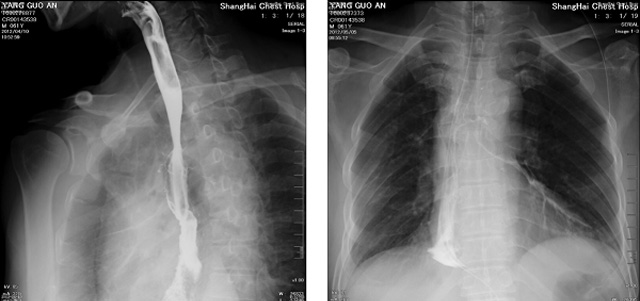

DR設(shè)備在2020年的新冠疫情中,加速了市場調(diào)整。以醫(yī)院為主的向二三級市場轉(zhuǎn)變。特別是小巧靈活的移動DR設(shè)計,填補CT和磁共振不能三維檢查的缺點,滿足內(nèi)科外科特別是骨科的影像診斷需求。還有懸吊DR設(shè)備CT斷層射線系統(tǒng)。使用錐束成像技術(shù)對整個脊柱和整個下肢進行了體積三維掃描。無需使用對比劑,即可使用X射線呼吸功能標(biāo)測來模擬模擬氣流和血流,以評估患者的肺動脈血栓。

數(shù)字化X線攝影依然是患者初篩的關(guān)鍵一環(huán)。靜態(tài)DR限制于探測器平臺。只能進行簡單普通的數(shù)字化影像檢查。胸部的疾病沒辦法篩查出微小的病灶。這樣導(dǎo)致DR慢慢的被CT跟磁共振代替。這樣造成了原來配套的數(shù)字化影像DR設(shè)備的 閑置。所以DR需要跟CT融合擴大DR的檢查使用場景。為DR提高更多的市場價值。X射線技術(shù)的原始形式和面向未來的可能性打破了CT成像和DR成像掃描技術(shù)之間的限制。融合成像趨勢更加明顯,多峰成像趨勢發(fā)展更加迅速。